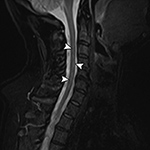

Figure 18B Figure 19A Figure 19B Figure 20

Truncation artifact Shading artifact Shading artifact Radiofrequency interference artifact

Truncation Artifact. (A) Sagittal STIR MR image demonstrates T2 hyperintense line (arrowheads) within the anterior spinal cord due to spinal-cord CSF interface

Truncation Artifact. (B) Corresponding axial MEDIC (multi-echo data image combination) MR image demonstrates normal appearance of the spinal cord.